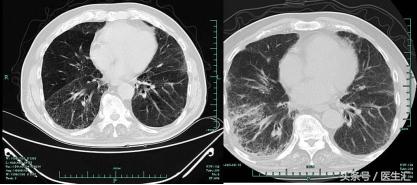

2013-9-25肺CT

2013-10-13 肺部CT:慢支、肺气肿。两肺间质性病变,对照13.9.25老片右肺斑片影增多,感染考虑。右上肺钙化灶。